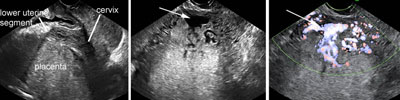

Placenta previa

Click the image to magnify it

Legend:Placenta previa

Reference(s):Oyelese Y. Placenta previa: the evolving role of ultrasound. Ultrasound Obstet Gynecol 2009;34(2):123–6. PubMed PMID: 19644942.

Ghi T, Contro E, Martina T, Piva M, Morandi R, Orsini LF, Meriggiola MC, Pilu G, Morselli-Labate AM, De Aloysio D, Rizzo N, Pelusi G. Cervical length and risk of antepartum bleeding in women with complete placenta previa. Ultrasound Obstet Gynecol 2009;33(2):209–12. PubMed PMID: 19173235.

Oppenheimer L, Holmes P, Simpson N, Dabrowski A. Diagnosis of low-lying placenta: can migration in the third trimester predict outcome? Ultrasound Obstet Gynecol 2001;18(2):100–2. PubMed PMID: 11529986.

Taipale P, Hiilesmaa V, Ylöstalo P. Transvaginal ultrasonography at 18-23 weeks in predicting placenta previa at delivery. Ultrasound Obstet Gynecol 1998;12(6):422–5. PubMed PMID: 9918091.